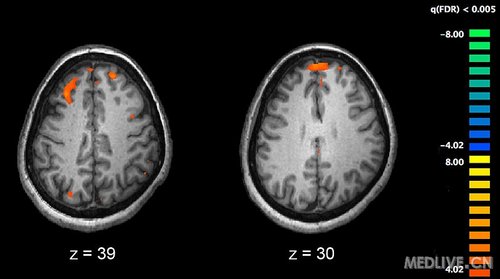

Image showing brain areas more active in controls than in schizophrenia patients during a working memory task during a fMRI study. Two brain slices are shown.